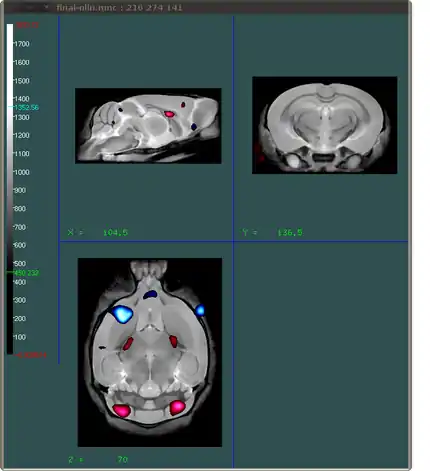

What we want to do is create an image that shows which areas of the brain have a certain t-statistic related to them. Ideally we want to show areas that have negative t-stats and positive t-stats using different colours. The end result should look something like this:

You can load multiple files into Display. In the example above the red shows areas where the t-statistics are at least 4 (and thus positive), and the blue areas indicate areas where the t-statistics are at most -4. All this information comes from one file: the tstats.mnc file. In order to create two different colours using that one file, you will have to load it in twice in Display. That is the first step

In Display, on the left side of the screen you see a slider for the colour which acts on the colours of the current visible layer. After you have switched the "under colour" to transparent, you can drag the indicators for the lower and upper colour to the desired levels. You can see that with the transparency turned on, as soon as you change the visible colour range, the next layer (in default "hot metal" colours) shows up.

All of what we have done so far is work on the "top" layer, which is the last argument to Display (tstats.mnc in this example). The three arguments we gave it in the beginning were final-nlin.mnc, tstats.mnc and tstats.mnc again. We will now go to the second layer (tstats.mnc) and use that layer to show the negative t-statistic values.

In this case, make sure that you drag the indicator for the top/upper end of the displayed range below the indicator for the lower/bottom end of the range.

The last things we need to do is change the colour of the brain (gray looks better with the blue and red), get rid of the cursor that is visible in, and make the interpolation of the layers look better.